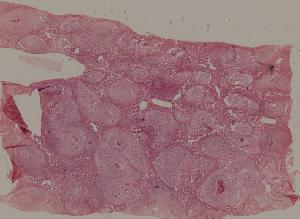

84.Graves disease